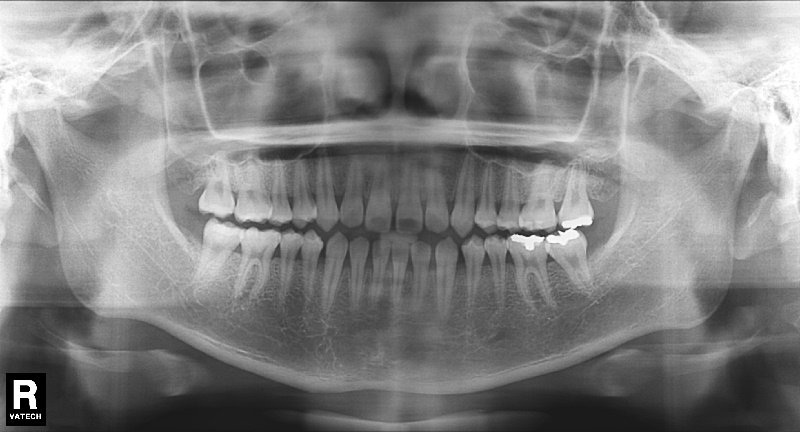

치료 전 사진입니다.